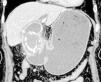

A 78-year-old woman presented with 2 days of postprandial vomiting. Physical examination revealed normal vital signs and a non-tender abdomen. Computed tomography scans identified a 3 cm calcified mass embedded in the first portion of the duodenum, causing gastric outlet obstruction (Fig. 1). Upper endoscopy confirmed a large stone impacted in the duodenum (Fig. 2). Based on the diagnosis of Bouveret’s syndrome, the patient underwent open enterolithotomy, cholecystectomy, and cholecystoduodenal fistula repair. The postoperative course was uneventful. Bouveret’s syndrome, first described in 1896 by the French physician Leon Bouveret, is characterized by the presence of a large stone obliterating the duodenal lumen or pylorus due to the formation of a bilioenteric fistula. Attachment of the inflamed gallbladder to the gastrointestinal tract, followed by an ischemic rupture and mechanical stress from gallstones, may cause the fistula. Although endoscopic electrohydraulic lithotripsy has been used worldwide, most cases require surgical intervention. The present case highlights the importance of early recognition of Bouveret’s syndrome to improve outcomes and reduce the associated high mortality.